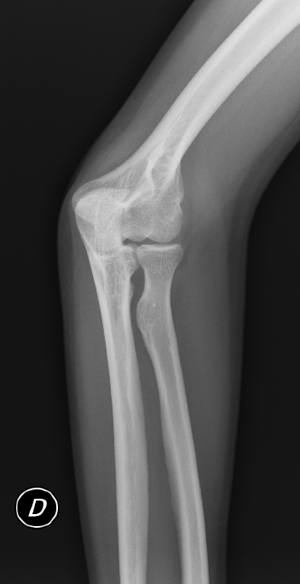

En RX simple no se aprecian claras líneas de fractura (figura 1 y figura 2), y ante la duda se decide realizar proyecciones adicionales para intentar despejar cabeza de radio. Se realizan dos proyecciones adicionales: oblicua de codo (oblicuando todo el cuerpo del paciente, para no movilizar el codo por dolor), y perfil de codo angulado el tubo caudalmente entre 10-15 grados. En ambas proyecciones se visualiza una clara fractura del mismo (figura 3 y figura 4).

Fractura de la cabeza del radio con afectación articular y sin luxación.

(figura 4)